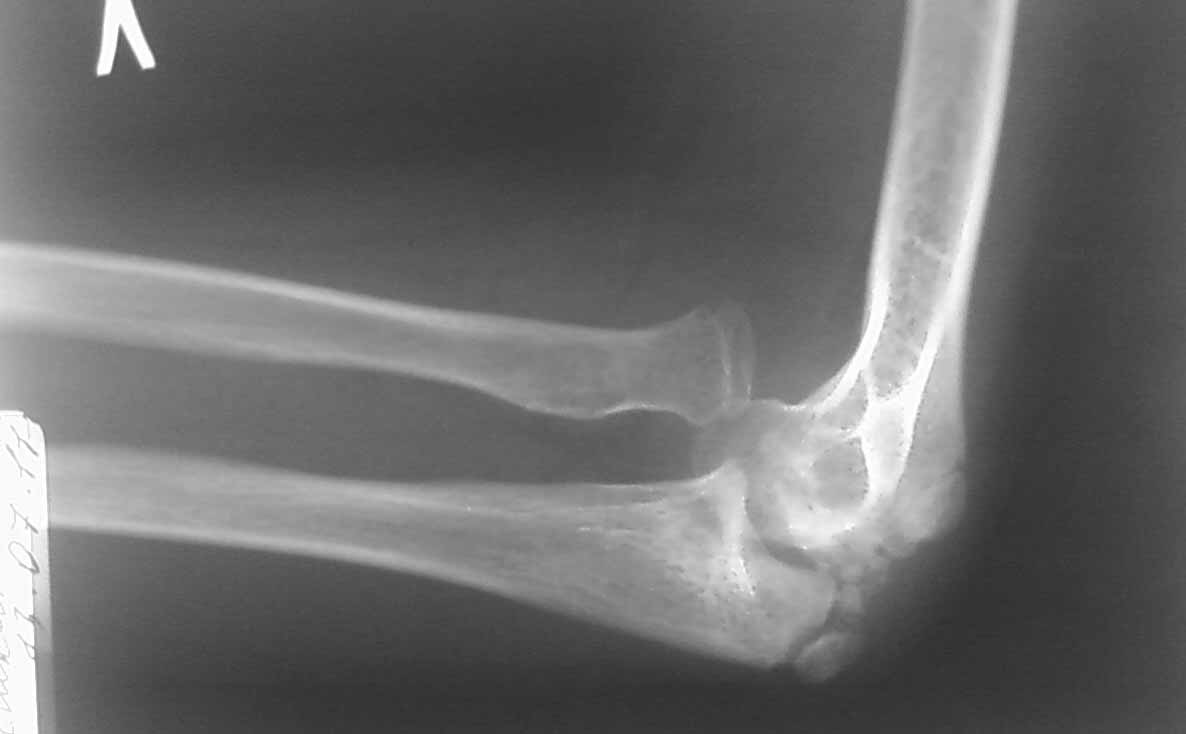

Re: Вальгусная деформация локтевого сустава у ребенка

Снимок в боковой проекции не получилось сразу отправить.